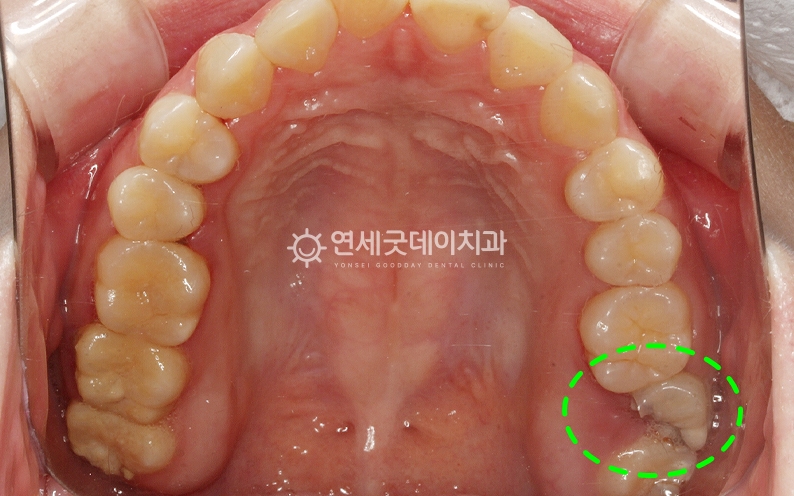

● 담당과 : 보존과 어금니 부위의 큰 충치를 주소로

#27, 36 부위에 큰 충치가 관찰되며

두 부위 모두 발치를 고려할 정도로 큰 충치였으나 또한 사진상 표시된 부위의 인접 치아는

신경치료를 통해 손상된 신경관을 제거 및 소독한 뒤 환자분은 치아 머리가 많이 손상된 상태였기 때문에

자연치아 살리기 과정 중 이후 약해진 치아를 보호하고

이어서 #27 부위도 신경치료를 진행하였으며

발치까지 고려할 만큼 심한 충치였음에도 연세굿데이치과는 오랫동안 자연치아 살리기 진료를 긴 치료 받으시느라 고생 많으셨습니다 :) ※ 모든 사진은 본인의 동의를 얻어 동일조건에서 촬영하였으며 |